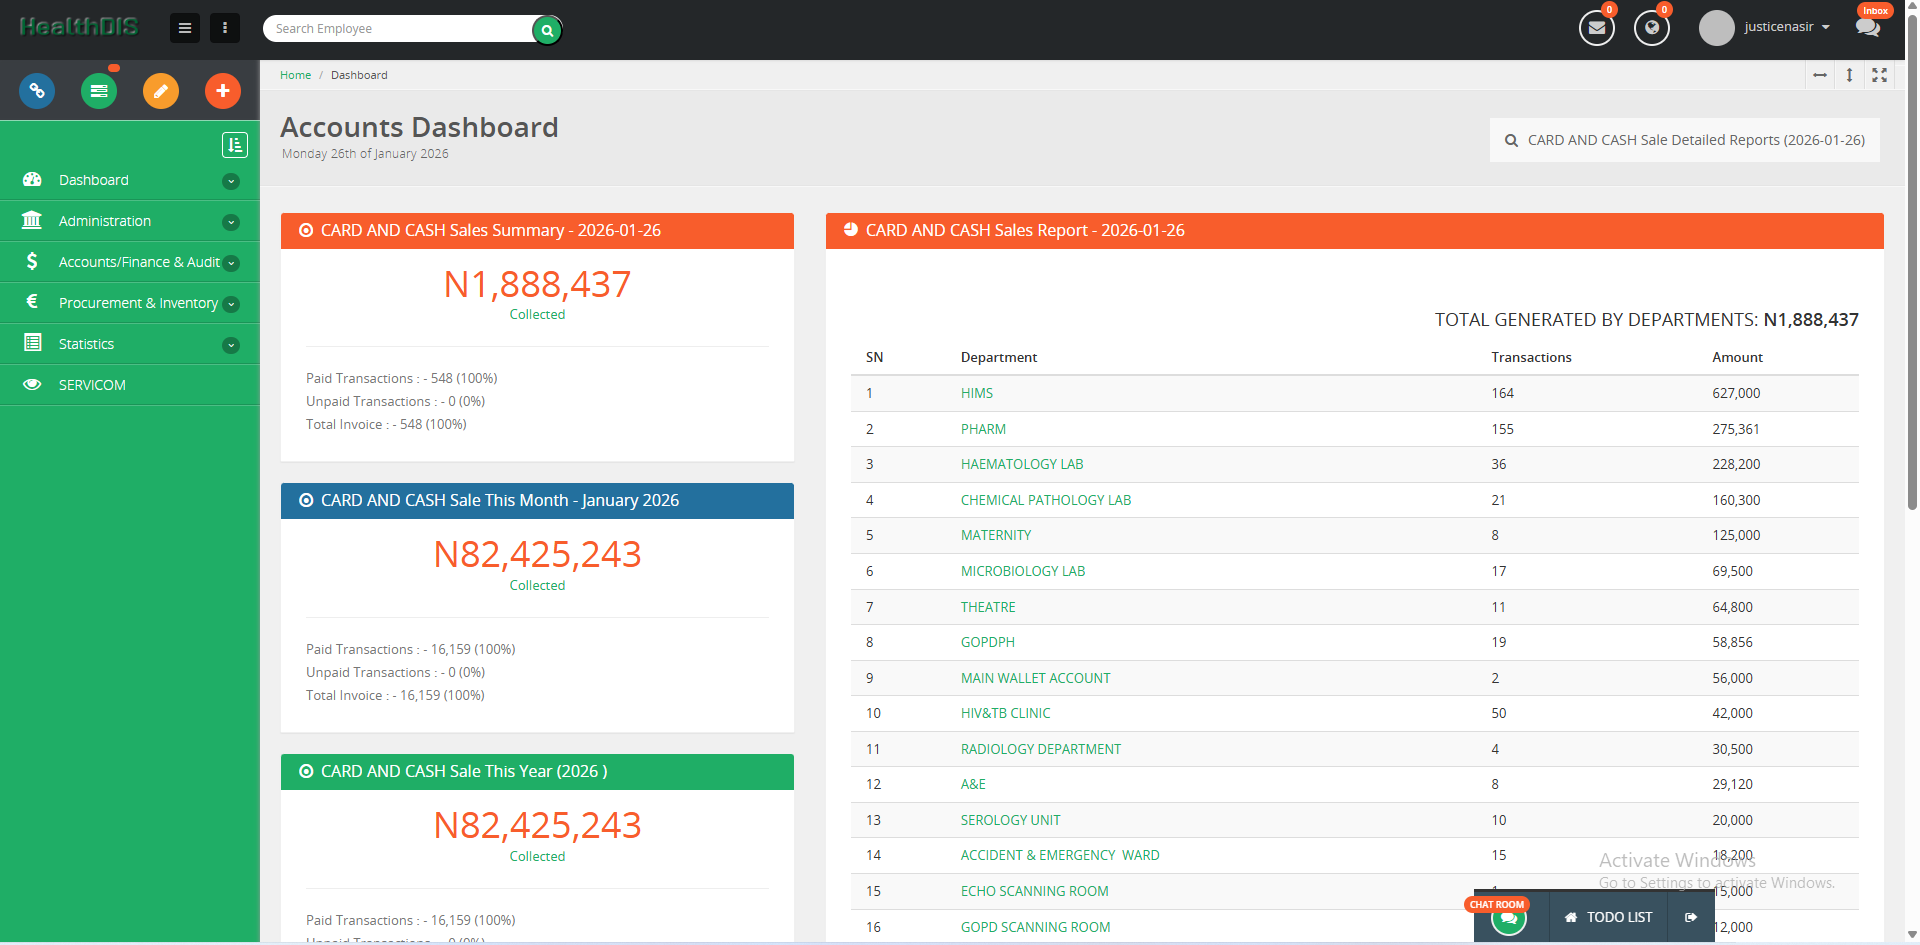

With our EHR, seamlessly manage clinical operations, administrative workflows, and financial services efficiently in one integrated platform.

Manage doctors, nurses, pharmacists, and laboratory services efficiently through a centralized clinical system.

Securely accept and manage patient payments with seamless billing and transaction tracking.

Manage financial operations, administrative activities, and system configurations.

CONTACT US CONTACT USOur platform simplifies financial management by securely tracking all transactions and providing detailed audit reports for future use.

Accessing patient diagnosis statistics is easy. Our software tracks all diagnoses and investigations for each patient, allowing you to visit the statistics module and download data for research purposes.